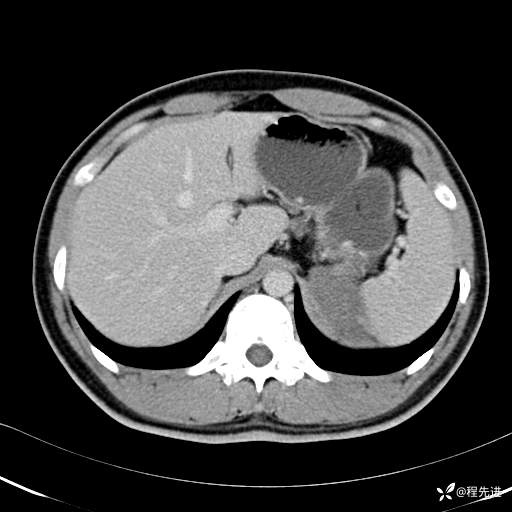

CT平扫:(CT值:平扫,27HU,动脉期,27HU,门静脉期,31HU,平衡期,32HU)

CT增强: